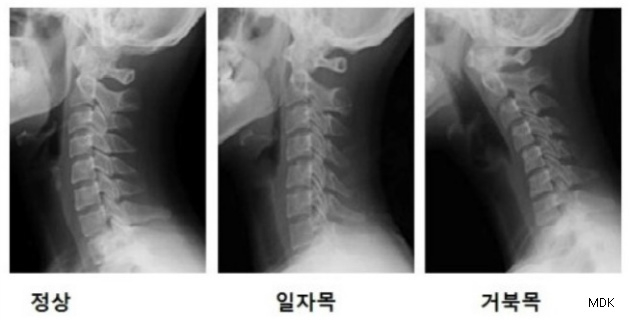

과거 중장년층에게 찾아 오던 '일자목증후군'이 최근 컴퓨터와 스마트폰 사용으로 발생연령이 젊은층으로 이동하면서 환자수도 급증하는 것으로 나타났다.

국민건강보험 일산병원 재활의학과 이장우 교수는 “일자목증후군은 잘못된 자세와 동작이 원인이 되고 이러한 요소들이 장기간 축적되어 골격의 변형까지 일으키는 질환"이라며 “근래 컴퓨터나 스마트폰 사용이 일상화 되면서 발생 연령이 점차 젊어지고 있다”고 설명했다.

‘일자목증후군’을 방치할 경우 “목 부위 통증뿐 아니라 두통이나 어깨 통증까지 유발할 수 있고 나이가 들면 구조물들의 비가역적 변화를 야기해 통증이 더 심해질 수 있다"며 "목 척추나 디스크 등의 퇴행성 변화를 초래하여 추간판탈출증이나 심한 경우 경추척수증과 같은 신경증상을 일으킬 수 있다”고 설명했다.